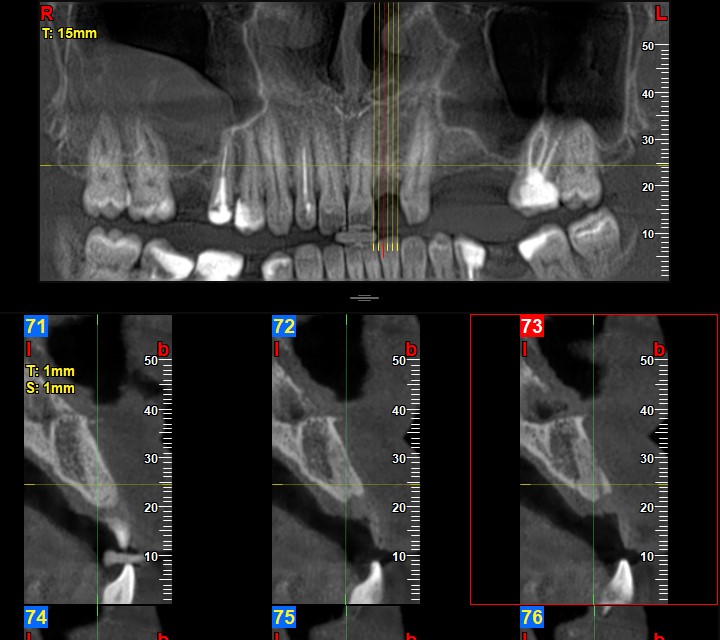

Втори етап: Хирургичен етап – поставяне на имплантите. Поставянето на импланти се извършва в строги стерилни условия с частична упойка. Всичко което ще се извършва ката допълнителна хирургическа намеса (екстракция на зъб, повдигане на синус, костна аугументация, добавяне на кост, добавяне на PRF и др. ) се обсъждат предварително.